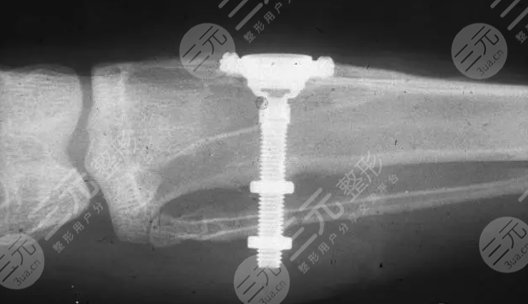

国产的种植牙要多少钱一个?为啥这么贵,科普解答!

相信每一个人都希望自己能够拥有一颗特别好看的牙齿,把这样会使整个人看起来特别的好看又有自信,但是有许多爱美人士因为各种的原因导致自己的牙齿出现了缺失的情况。而当牙齿缺失之后会使我们和别人交谈的时候,并没有那么有自信,所以说很多人就想要开始通过种植牙的方式来进行改善。那么很多人就想要了解一下国产的种植牙要多少钱一个?为啥这么贵,科普解答!下面就让我们一起来了解一下吧。

国产的种植牙要多少钱一个

在正常情况下来说,进行一科国产种植牙的价格大概是在5000元到三万元之间不等,但是的价格是没有办法进行固定的,会根据许多外界的因素而导致价格有这非常大的波动,以下几个因素就是影响到价格最主要的原因。